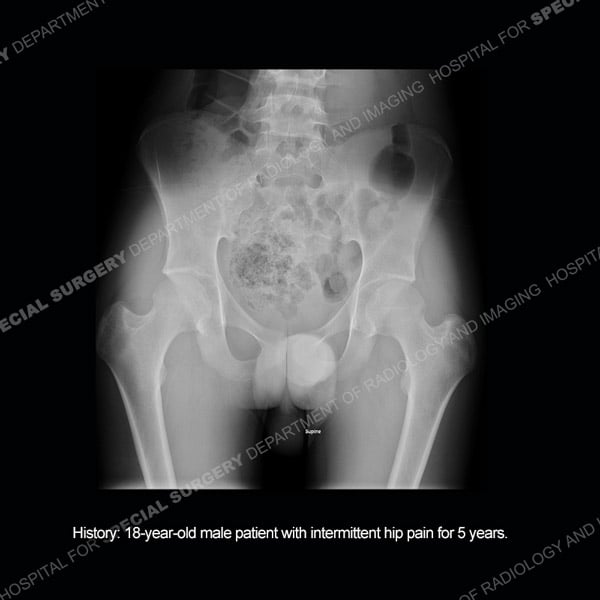

Featured Case of the MonthCase 213: 18-year-old male patient with intermittent hip pain for 5 years.